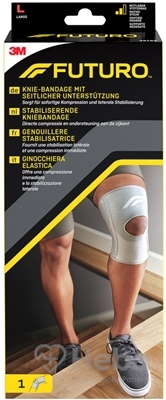

QMED REFLEX, Otvorená kolenná ortéza, veľ. M+

Ortéza Reflex sa používa pri miernej nestabilite kolenného kĺbu rôznej etiológie.

VLASTNOSTI PRODUKTU.

-ortéza je vyrobená z priedušného materiálu s priestorovou (dištančnou) štruktúrou, tento materiál odvádza vlhkosť, zlepšuje komfort používania,

-bočnice umožňujú tvarovanie do anatomického tvaru končatiny, čo zlepšuje kontrolu pohybu a komfort používania,

-odnímateľné pásky umožňujú aplikáciu vpravo aj vľavo a značky na nich zaisťujú správne pripútanie pacienta,

-jemný, nekrčivý materiál so špeciálnym napätím zabraňuje podráždeniu a tlaku v kolene,

-všetky uzavreté verzie sú navyše vybavené stabilizačným krúžkom kolenného kĺbu, ktorého polohu a dĺžku je možné prispôsobiť potrebám a typu dysfunkcie,

-otvorené a uzavreté verzie ortézy,

-dĺžka ortézy 31 cm.

VEĽKOSTI:

XS S M L XL XXL XXXL**

Obvod stehna * (cm) 30-36 36-44 44-50 50-57 57-64 64-72 72-78

* meriame 15 cm nad stredom kolien

** platí pre otvorenú ortézu